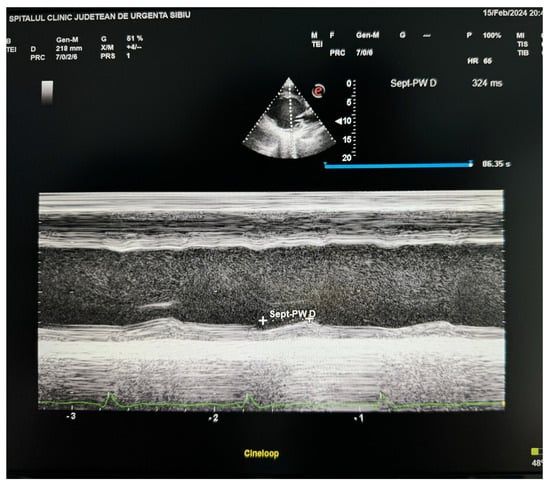

2.2. Echocardiography

| Septal–posterior wall delay | M mode parasternal LV view | ≥130 msec | Rapid, widely available | More affected by passive motion or tethering; akinesis provides difficulty | |